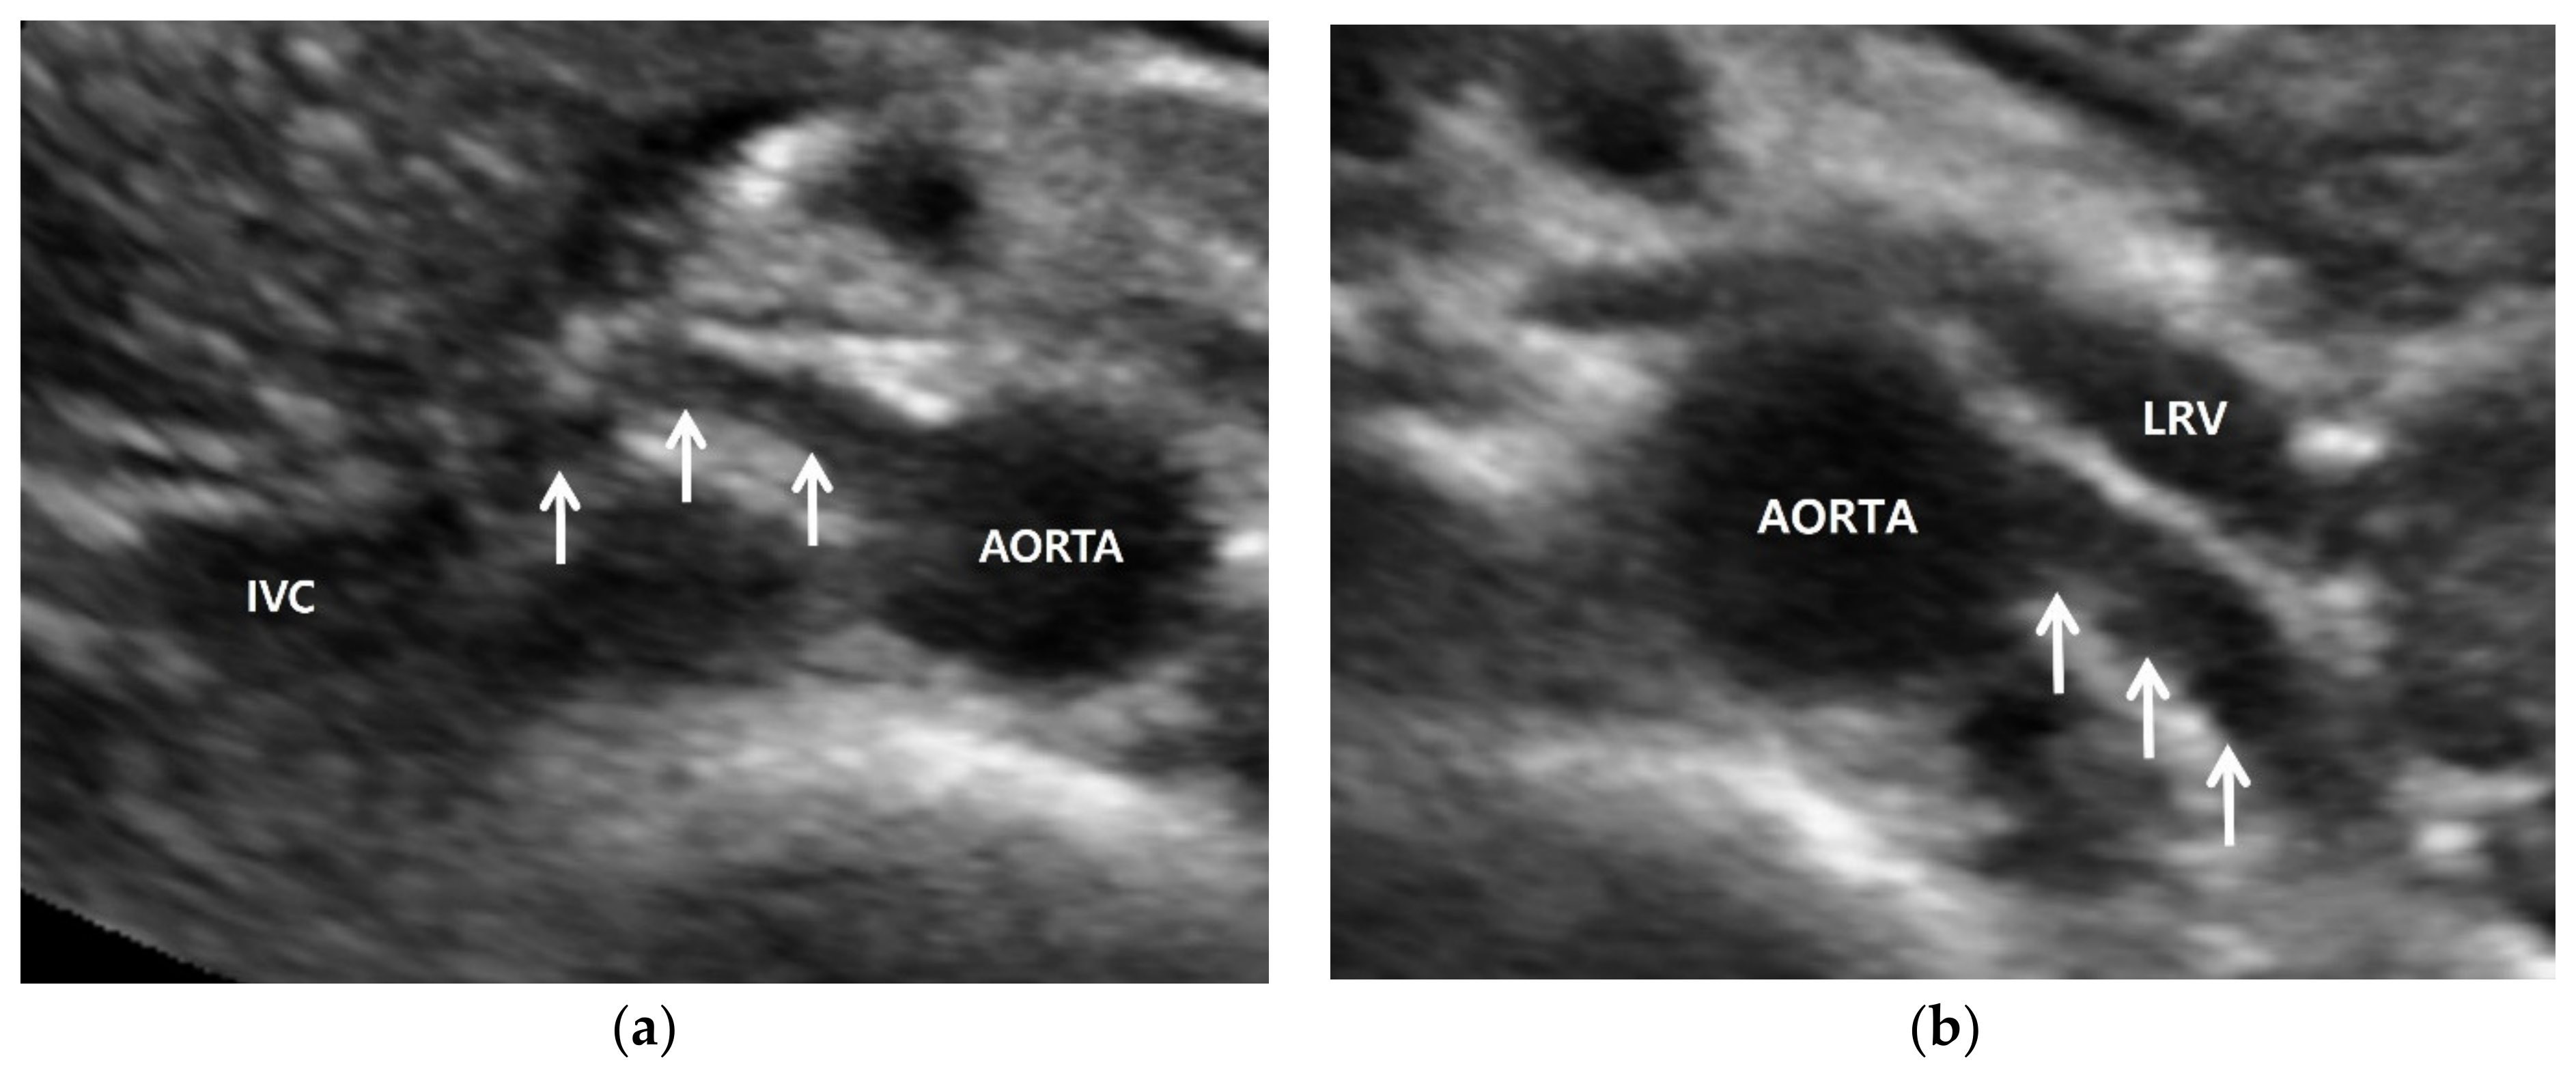

4. Renal Artery US: Imaging Techniques

Figure 1.

Normal anatomy of renal artery. (a) Gray-scale US axial image shows right renal artery (arrows) arising 10 o’clock from the aorta. It shows a short segmental angulation behind the inferior vena cava (IVC); (b) gray-scale US axial image shows left renal artery arising 4 o’clock from the aorta. It is located below the left renal vein (LRV) and is traveling away from the transducer without angulation.